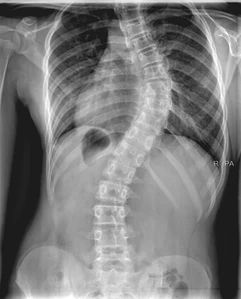

What is pediatric scoliosis?

Scoliosis is a sideways curvature of the spine which may cause the spine to be in the shape of a C or S instead of being straight.